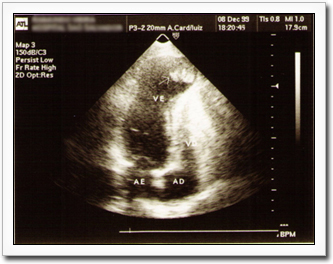

Echocardiogram findings in patients series demonstrate aneurysms in 8.5% to 55% of patients, with higher prevalence when the series includes patients with advanced disease. Thrombus formation (as seen in this echocardiogram) is common and can lead to emboli and strokes. Photo courtesy Dr. Anis Rassi Jr.